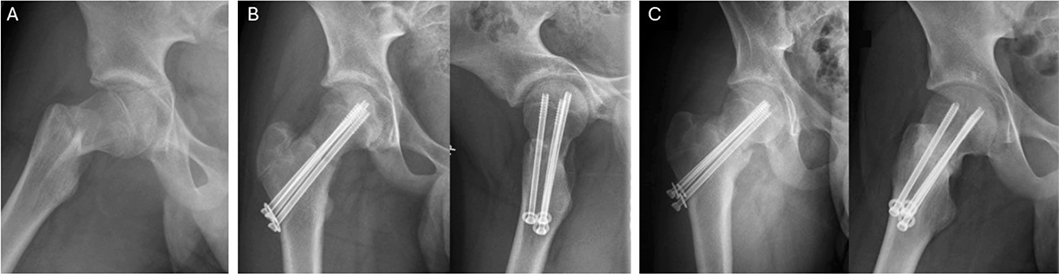

39 patients were interviewed only, without follow-up invitation: 79% (31/39) scored 48 on OHS, and the remaining 21% (8/39) scored ≥ 44. Among them, patient no. 1 with Ratliff I AVN scored 47 on OHS at 5-year follow-up, despite the fact that on last clinical examination 3 years post-accident, gait was found to be affected, with significant range of motion (ROM) limitations (flexion 80°, internal rotation 5°, external rotation 40°, and abduction 10°) and total collapse of the femoral head. However, during the interview she expressed having hip pain 1–2 times a month with no limitations in daily activities due to impaired hip function. Regardless of this discrepancy between objective findings and subjective view on good outcome, we considered the patient’s outcome as impaired due to her limited ROM, abnormal gait, and radiographic deformity. Patient no. 4 with nonunion scored 48 on OHS at 9-year follow-up and described no symptom/functional deficit (Figure 3). Patient no. 5 with hardware failure following screw fixation of Delbet II fracture scored 48 on OHS at 1-year-follow up. 4 patients with uncomplicated recovery described minor issues during interview: 2 had asymmetric gait (complete subtrochanteric), 1 had mild pain during long-distance running (complete subtrochanteric), and 1 had hip stiffness (Delbet II). 3 patients were dissatisfied with the cosmetic outcome of their treatment because of excessive scar formation.

Figure 3. (A) Primary radiograph showing a dislocated Delbet II fracture, (B) fracture alignment following operation, and (C) non-union 7 months post-injury